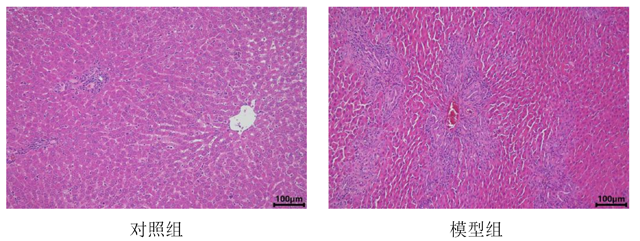

肝组织HE染色

在预定的时间点(如术后数天或数周),处死动物并取出肝脏组织进行病理学检查。观察肝脏的形态学变化,如肝小叶结构失常、纤维组织增生等。可采用血清学检测等方法评估肝功能的变化,如胆红素、转氨酶等指标。同时,可观察动物的黄疸情况,如皮肤、巩膜黄染等。详细如下表